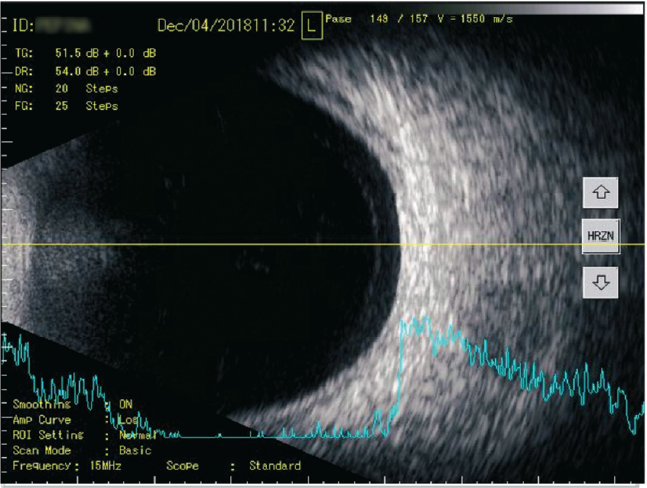

У пациентов обеих групп по окончании курса по данным комбинированного А- и В-сканирования топографические характеристики были постоянными: в 82 % случаев (р = 0,43) помутнения концентрировались в нижней половине СТ (рис. 3, 4).

Рис. 3. A- и B-сканирование пациентки П. при первичном обращении. В-скан: в поперечной проекции по меридиану 6 ч — умеренное количество помутнений в стекловидном теле. А-скан: 21 пик низкой эхогенности

Fig. 3. Initial treatment, Patient P.: B-scan: transverse projection along the meridian to 6 hours, moderate amount of “clouding” in the vitreous body. A-scan: 21 peaks of low echogenicity

При сканировании в В-режиме после курса лечения препаратом «Витрокап» в 32 % случаев отмечено уменьшение количества помутнений, что соответствовало снижению количества эхопиков на А-сканировании (рис. 4, 6, 8), в большинстве случаев (80 %, р < 0,05) происходило снижение высоты эхопиков при А-сканировании в зоне их максимальной концентрации (см. рис. 4, 8).